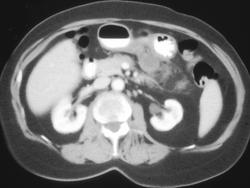

Diagnosis

Intrathoracic Stomach